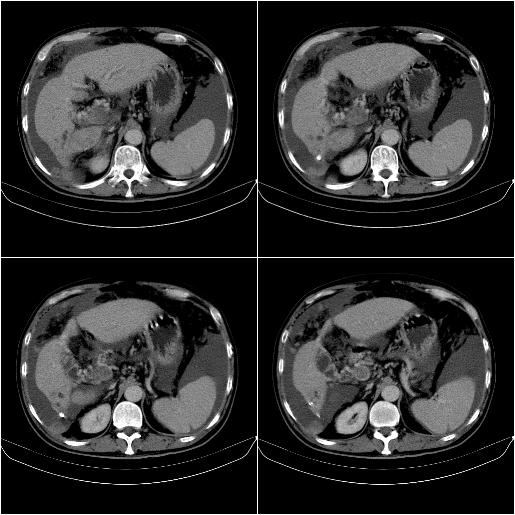

标题: CT21651:M,67Y,肝癌9月,介入术后3月。

m,67y,肝癌9月,介入术后3月。现腹胀、纳差、腹泻。

情况不好,门静脉癌栓、腹膜转移。

1)肝癌介入治疗术后碘油沉积不良。2)门静脉瘤栓形成,腹膜广泛性转移。3)肝硬化,脾大,腹水。4)慢性胆囊炎。